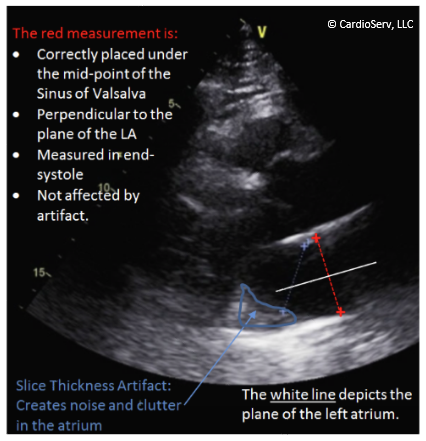

LA linear dimension

LA measurement

PLAX

When: end systole (atrium is largest)

Where: midpoint of sinus of valsalva

Measure perpendicular to annular plane, mid plane of mitral annulus to midpoint or superior wall, do not include LAA/PV